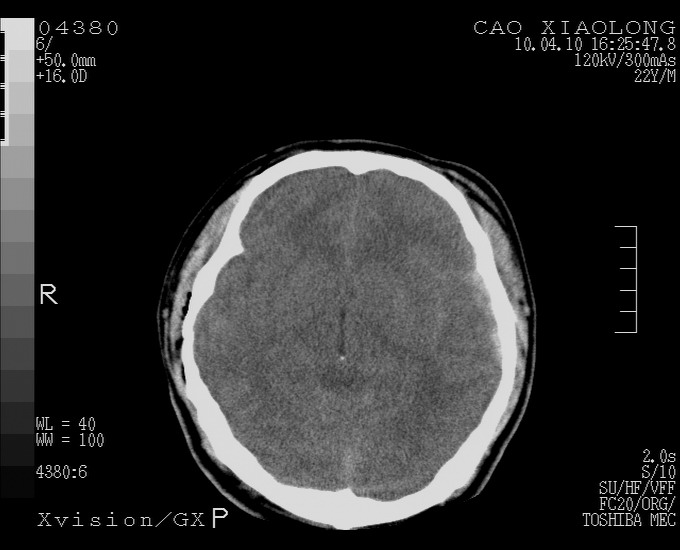

以下是引用随光逐影在2010-4-11 11:00:00的发言:[br]1)左侧额颞顶部硬膜下血肿。2)蛛网膜下腔出血。3)右侧颞顶部颅骨线形骨折。[br][br]20小时后复查:左侧额颞叶脑挫裂伤;左侧额颞顶部硬膜下血肿及蛛网膜下腔出血有吸收表现;右侧颞顶部颅骨线形骨折。[br]